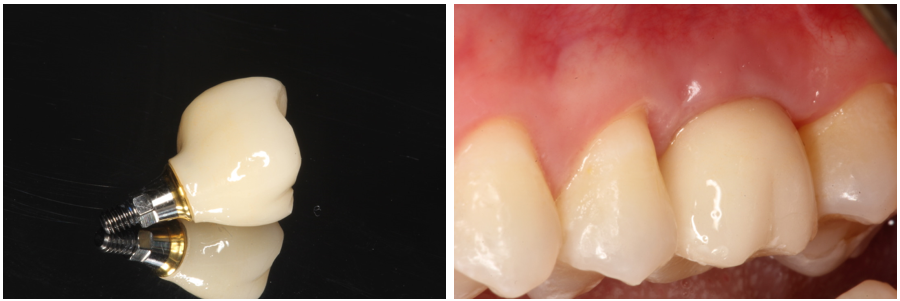

Enfim, um implante osseointegrável de 5.0 x 10 mm TS III (Osstem, Seul, República da Coréia) foi instalado (Figura 14). Após três meses foi feita a reabertura com enxerto de tecido conjuntivo do palato na vestibular e instalação de um cicatrizador (Figura 15). Um mês depois, um provisório foi instalado para promover o correto perfil de emergência gengival (Figura 16) e, então, foi utilizado um corpo de escaneamento (Osstem, Seul, República da Coréia), conforme Figura 16, para a realização do escaneamento para a moldagem digital. Uma coroa em dissilicato de lítio sobre pilar de titânio “Rigid” (Osstem, Seul, República da Coréia) foi confeccionada e parafusada sobre o implante com torque de 30 Ncm (Figura 17). Uma radiografia periapical final sugere a osseointegração do implante, a estabilidade do enxerto ósseo na região do seio maxilar e a perfeita adaptação protética após 12 meses (Figura 18).